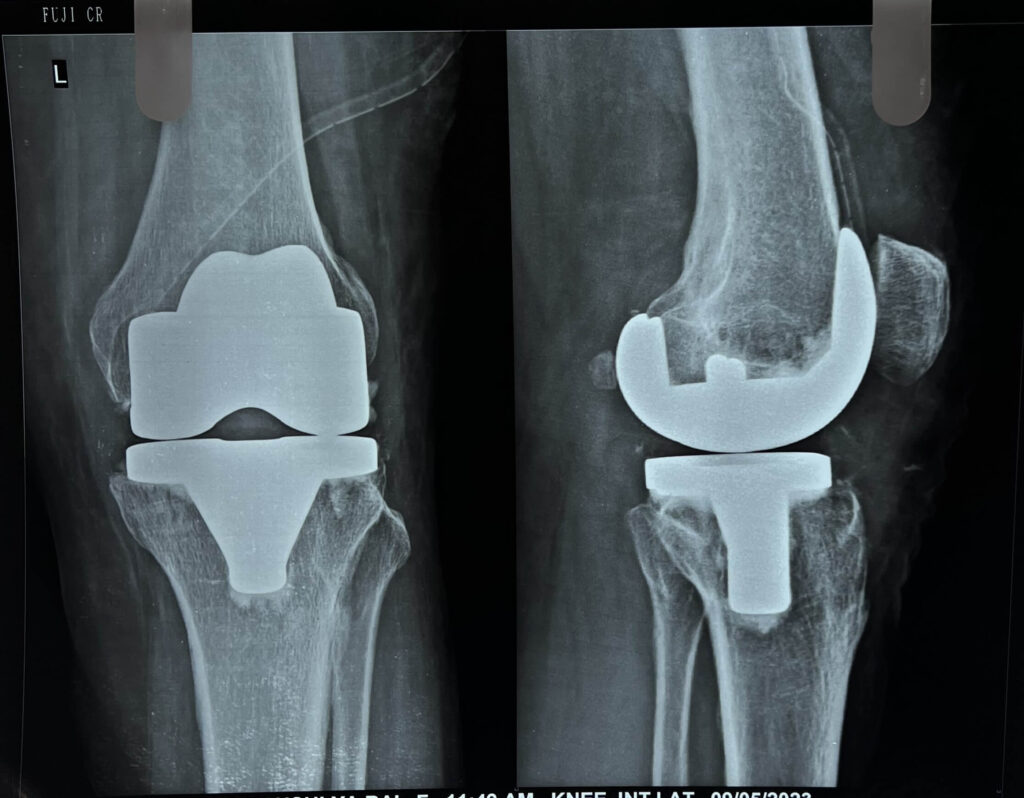

Total knee replacement (TKR) is a surgical procedure in which a damaged knee joint is replaced with an artificial joint, known as a prosthesis. It is usually performed for severe arthritis or other conditions that cause significant pain and limitation in knee function. After the surgery, the patient undergoes a period of rehabilitation to restore mobility, strength, and function. Here are some indications, precautions, and rehabilitation guidelines for total knee replacement:

4). Long-term durability: Knee replacement implants are designed to be durable and long-lasting. While the lifespan of an implant varies depending on factors such as the patient’s age, activity level, and implant type, most knee replacements can provide pain relief and functional improvement for 15 to 20 years or more. This long-term durability allows individuals to enjoy the benefits of the surgery for an extended period.